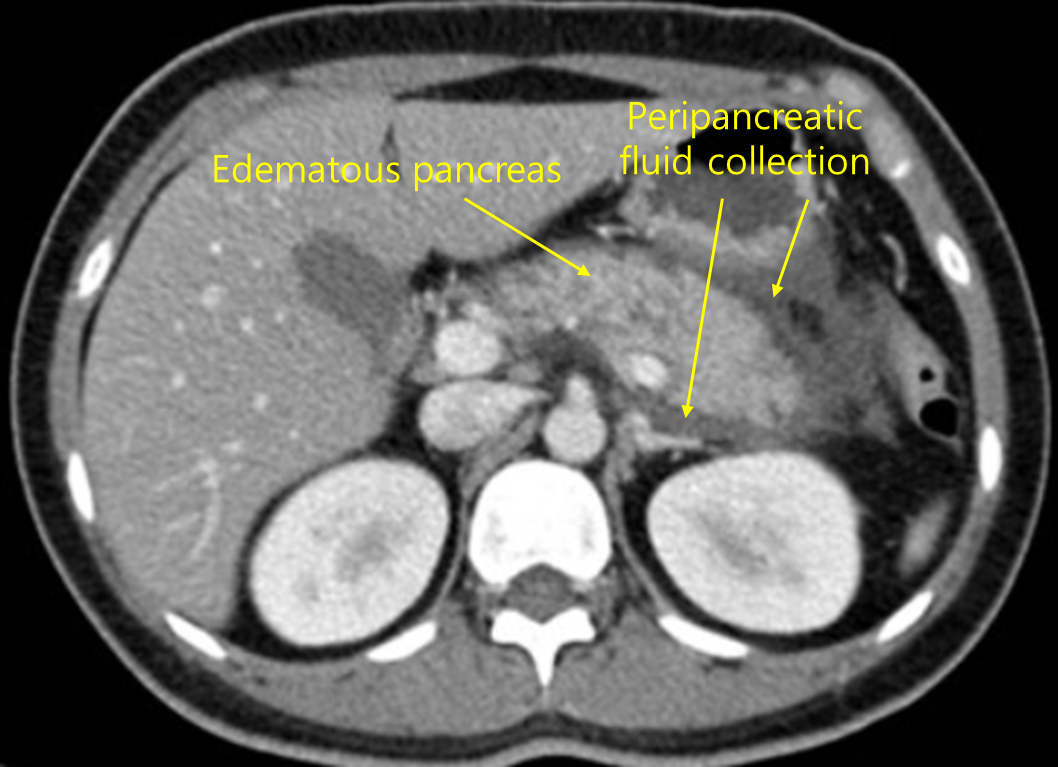

Img | CT: Peripancreatic fluid accumulation |

Hypertriglyceridemia, epigastric pain, amylase/lipase 상승, CT상 pancreas의 inflammation 소견으로 보아 급성 췌장염으로 진단할 수 있다.

• 급성 췌장염이 의심되어 촬영한 복부 CT상 pancreas 주위의 액체 저류가 있는 등 염증 소견이 확인되므로, 여러가지 임상양상과 조합했을 때 급성 췌장염으로 진단할 수 있다.

진단 | • US: 담석, 담관확장 확인 • CT: 췌장 실질의 edema, 췌장 근처 조직의 inflammation |